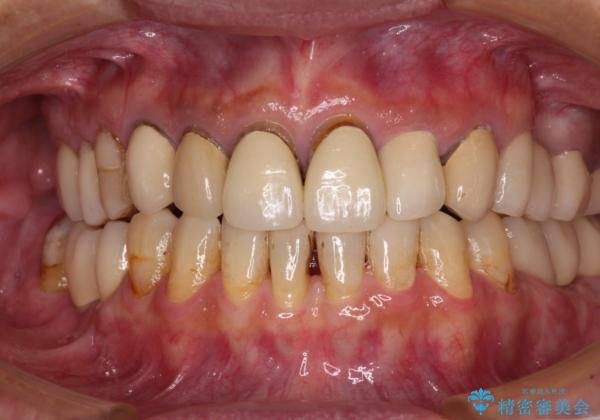

右下は奥歯が抜歯したスペースを塞いでしまい、左下はブリッジの支台歯の1つが破折している状態でした。

また、下顎前歯にはスペースがあり、コンポジットレジンでスペースを閉じている状態だったので、前歯のスペースを解消しつつ、奥歯にスペースを獲得するよう矯正治療を行うこととしました。

並行して左下にはインプラントを埋入し、上顎臼歯部の気になる部分も根管治療などを進めて行き、矯正治療を終えると同時に補綴治療を行うこととしました。

奥歯1歯分を動かすには時間がかかるため、矯正治療には思いの外時間がかかりました。

痛みのある奥歯は必要に応じて根管治療を行い、左下インプラントは角化歯肉の移植により清掃性を向上させ、気になっていた部分をしっかりと改善させることができました。